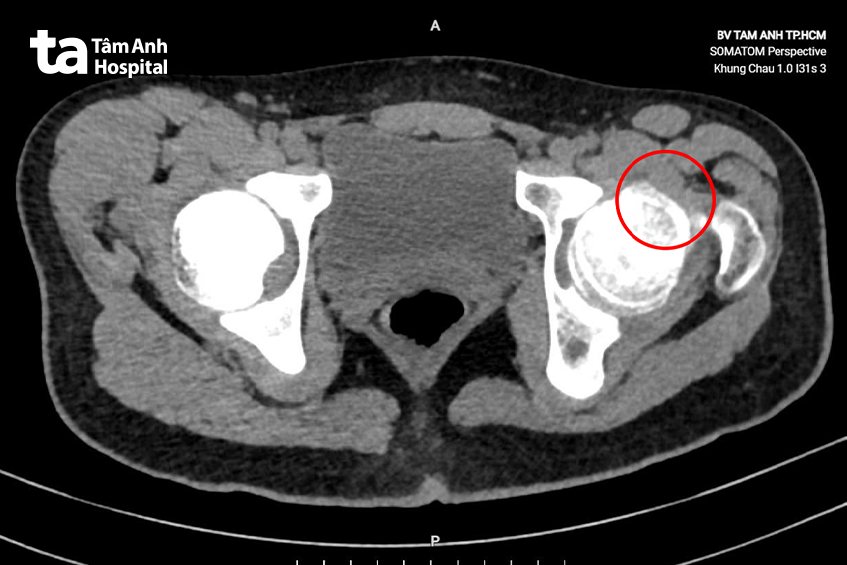

ThS.BS.CKI Nguyễn Xuân Trường, Trung tâm Chấn thương Chỉnh hình, Bệnh viện Đa khoa Tâm Anh TP HCM, cho biết kết quả siêu âm và chụp CT ghi nhận khớp háng bệnh nhi xuất hiện một mô xương bất thường, nhô cao, kích thước khoảng 5 x 10 mm, chiếm gần hết diện tích phía trước của chỏm xương đùi. Bác sĩ chẩn đoán Phát mắc hội chứng cấn khớp háng. “Đây là một bệnh lý ít gặp, xảy ra khi xương hông phát triển bất thường không rõ nguyên do, làm xuất hiện một mảng xương nhô cao hơn ở chỏm xương đùi”, bác sĩ Trường nói thêm.